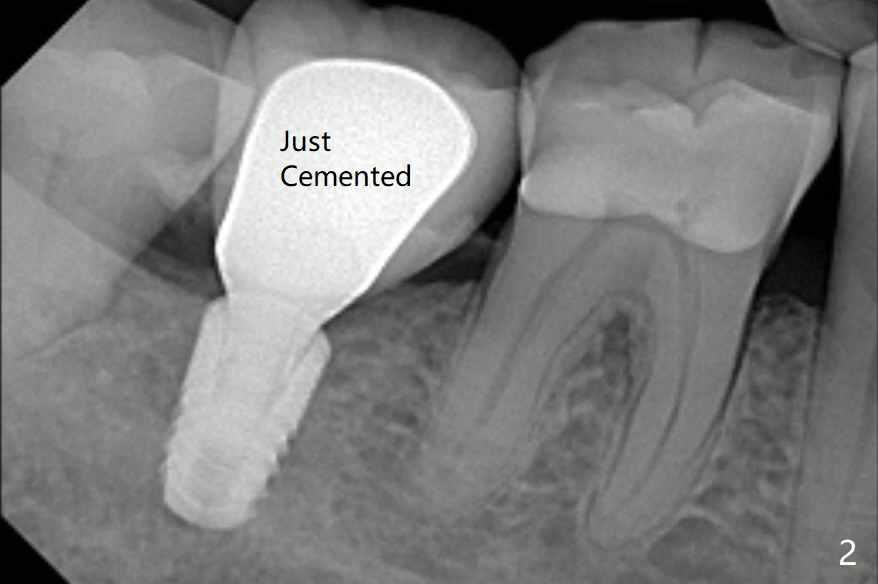

开场白病例

74岁男